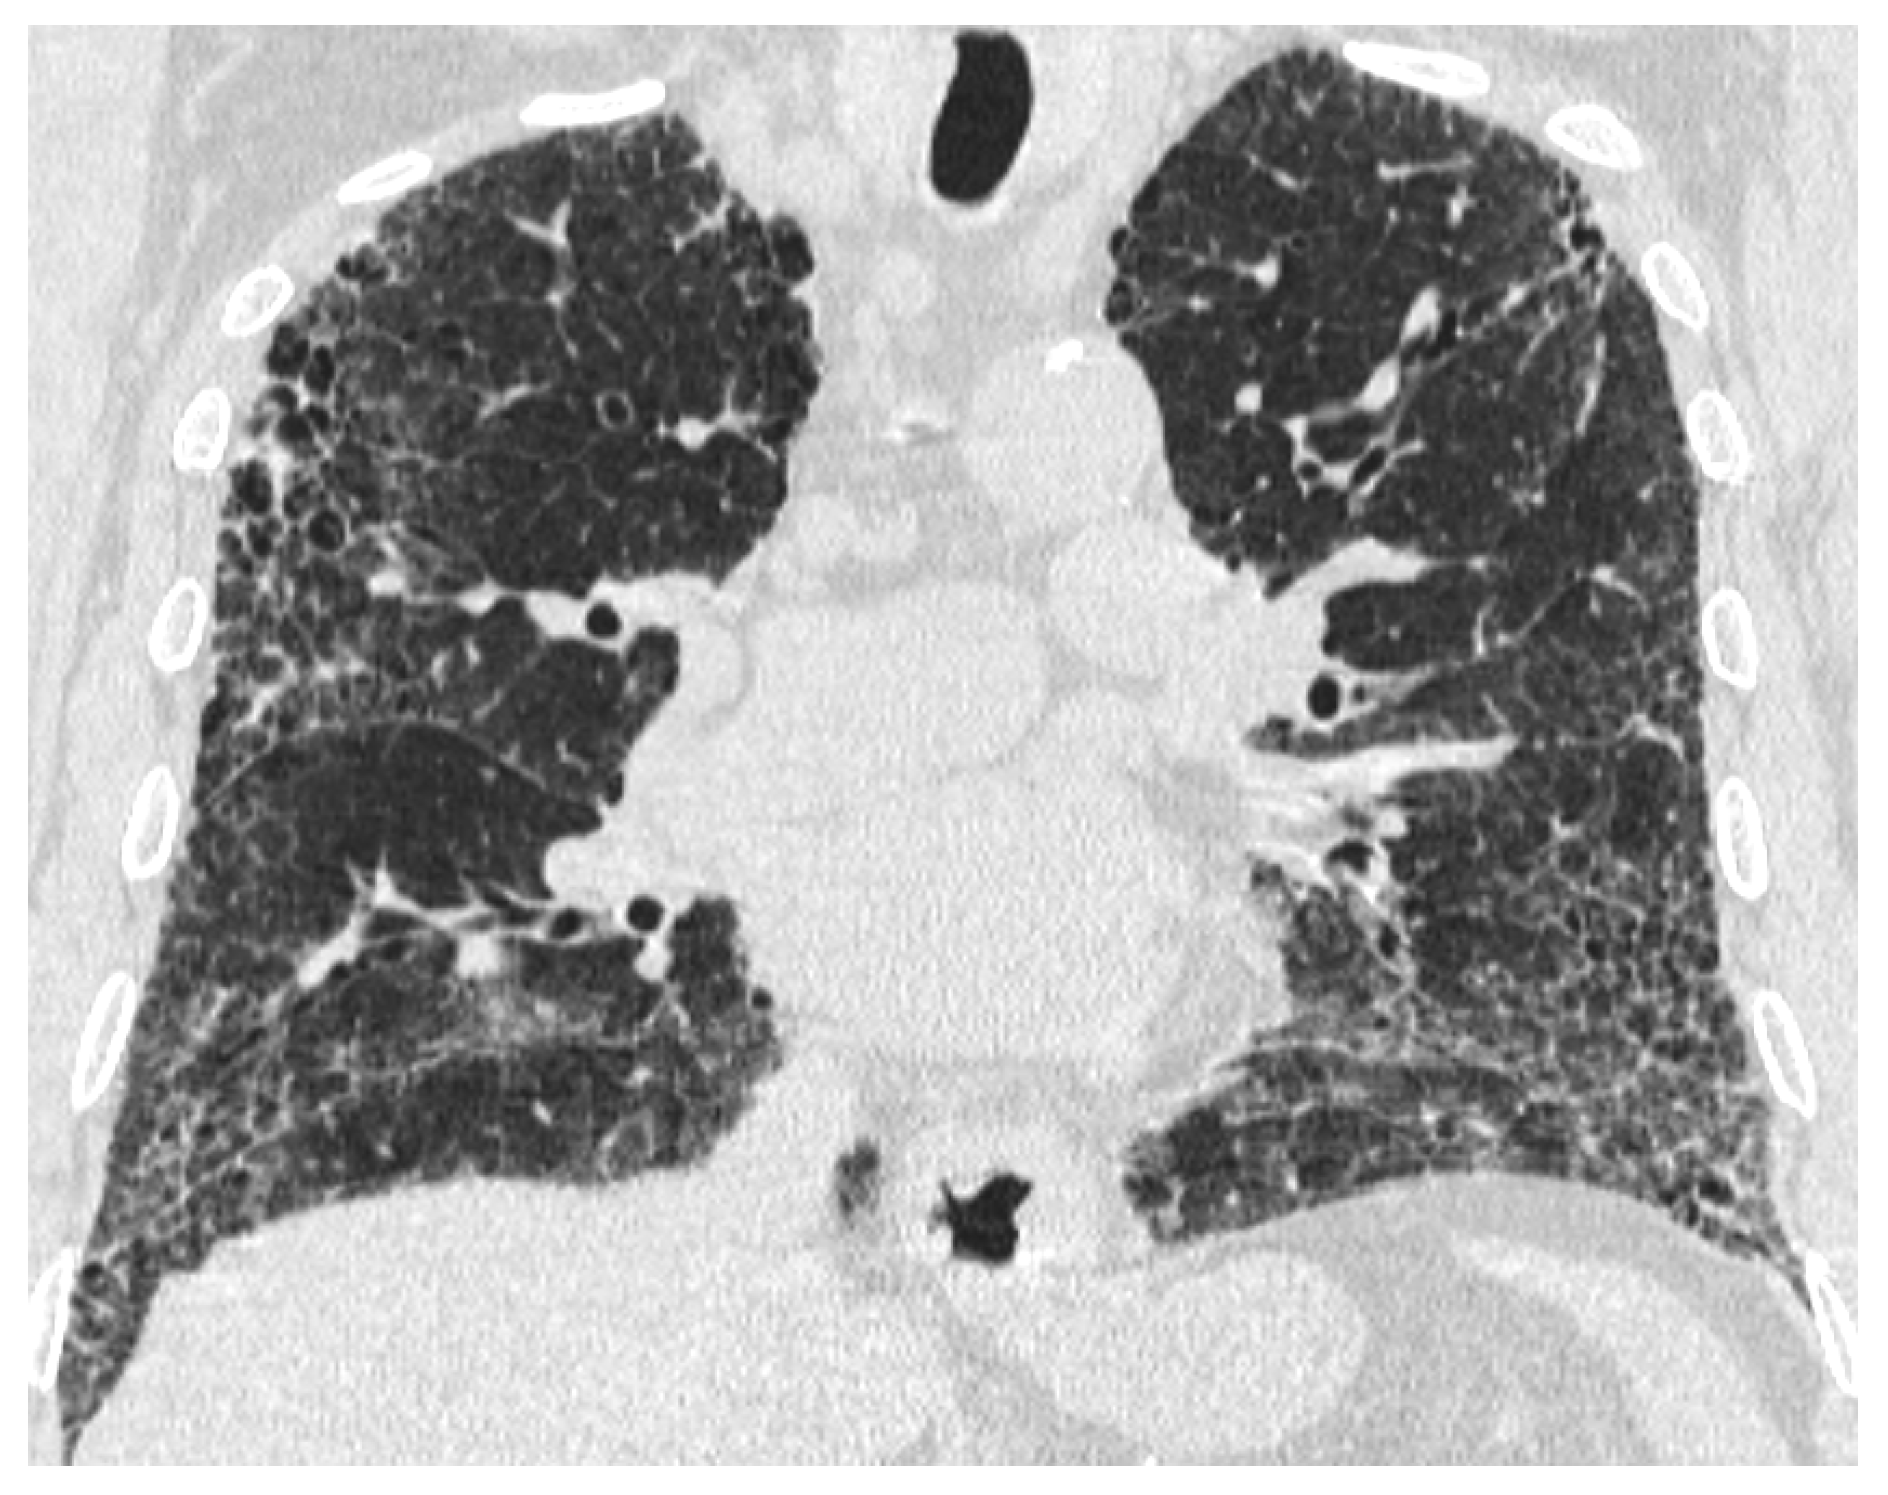

The Role of High-Resolution Lung Computed Tomography to Distinguish Between Fibrosing Hypersensitivity Pneumonitis and Usual Interstitial Pneumonia

3.2. HRCT Patterns in the Groups